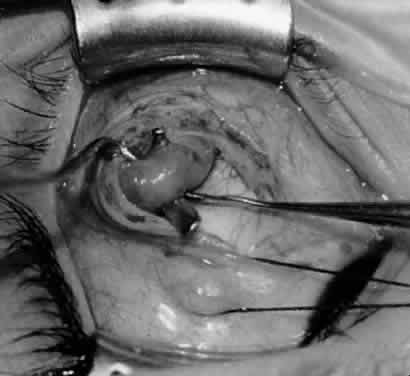

Fig. 10. The inferior oblique muscle is placed on the Green muscle hook. The exposed insertion is ready for myotomy, myectomy, disinsertion, placement of sutures for recession, or removal for the extirpation procedure.

Fig. 11. Sutures are placed into the insertion of the inferior oblique muscle before it is sectioned from the globe for the recession procedure.

Fig. 12. An Aebli scissor is placed beneath the inferior oblique muscle insertion before it is sectioned from the globe.

Fig. 13. The inferior oblique muscle is sectioned from the globe. A preplaced 6-0 Vicryl suture is attached to the insertion.